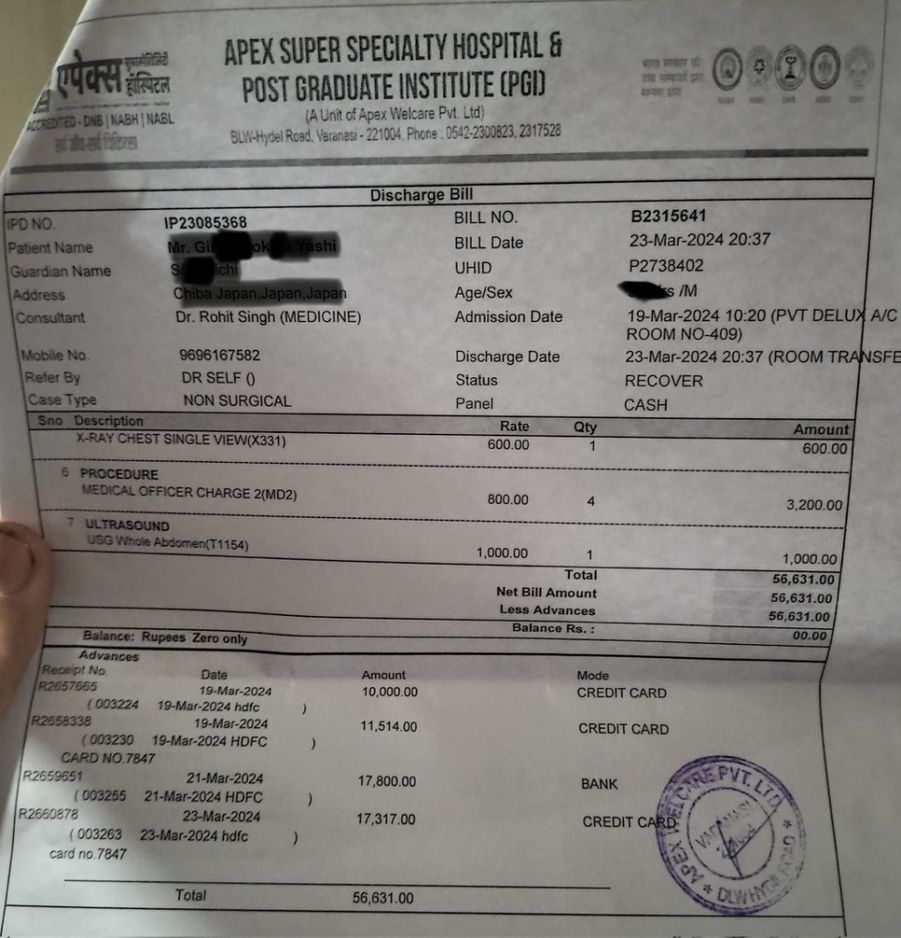

不仅如此,打点滴效果不好,他手臂肿得厉害。在蟑螂泛滥的病房住了4天,最终花费约152,980日圆(约7,470港元),没想到当初省下20卢比竟换来如此高昂的代价。